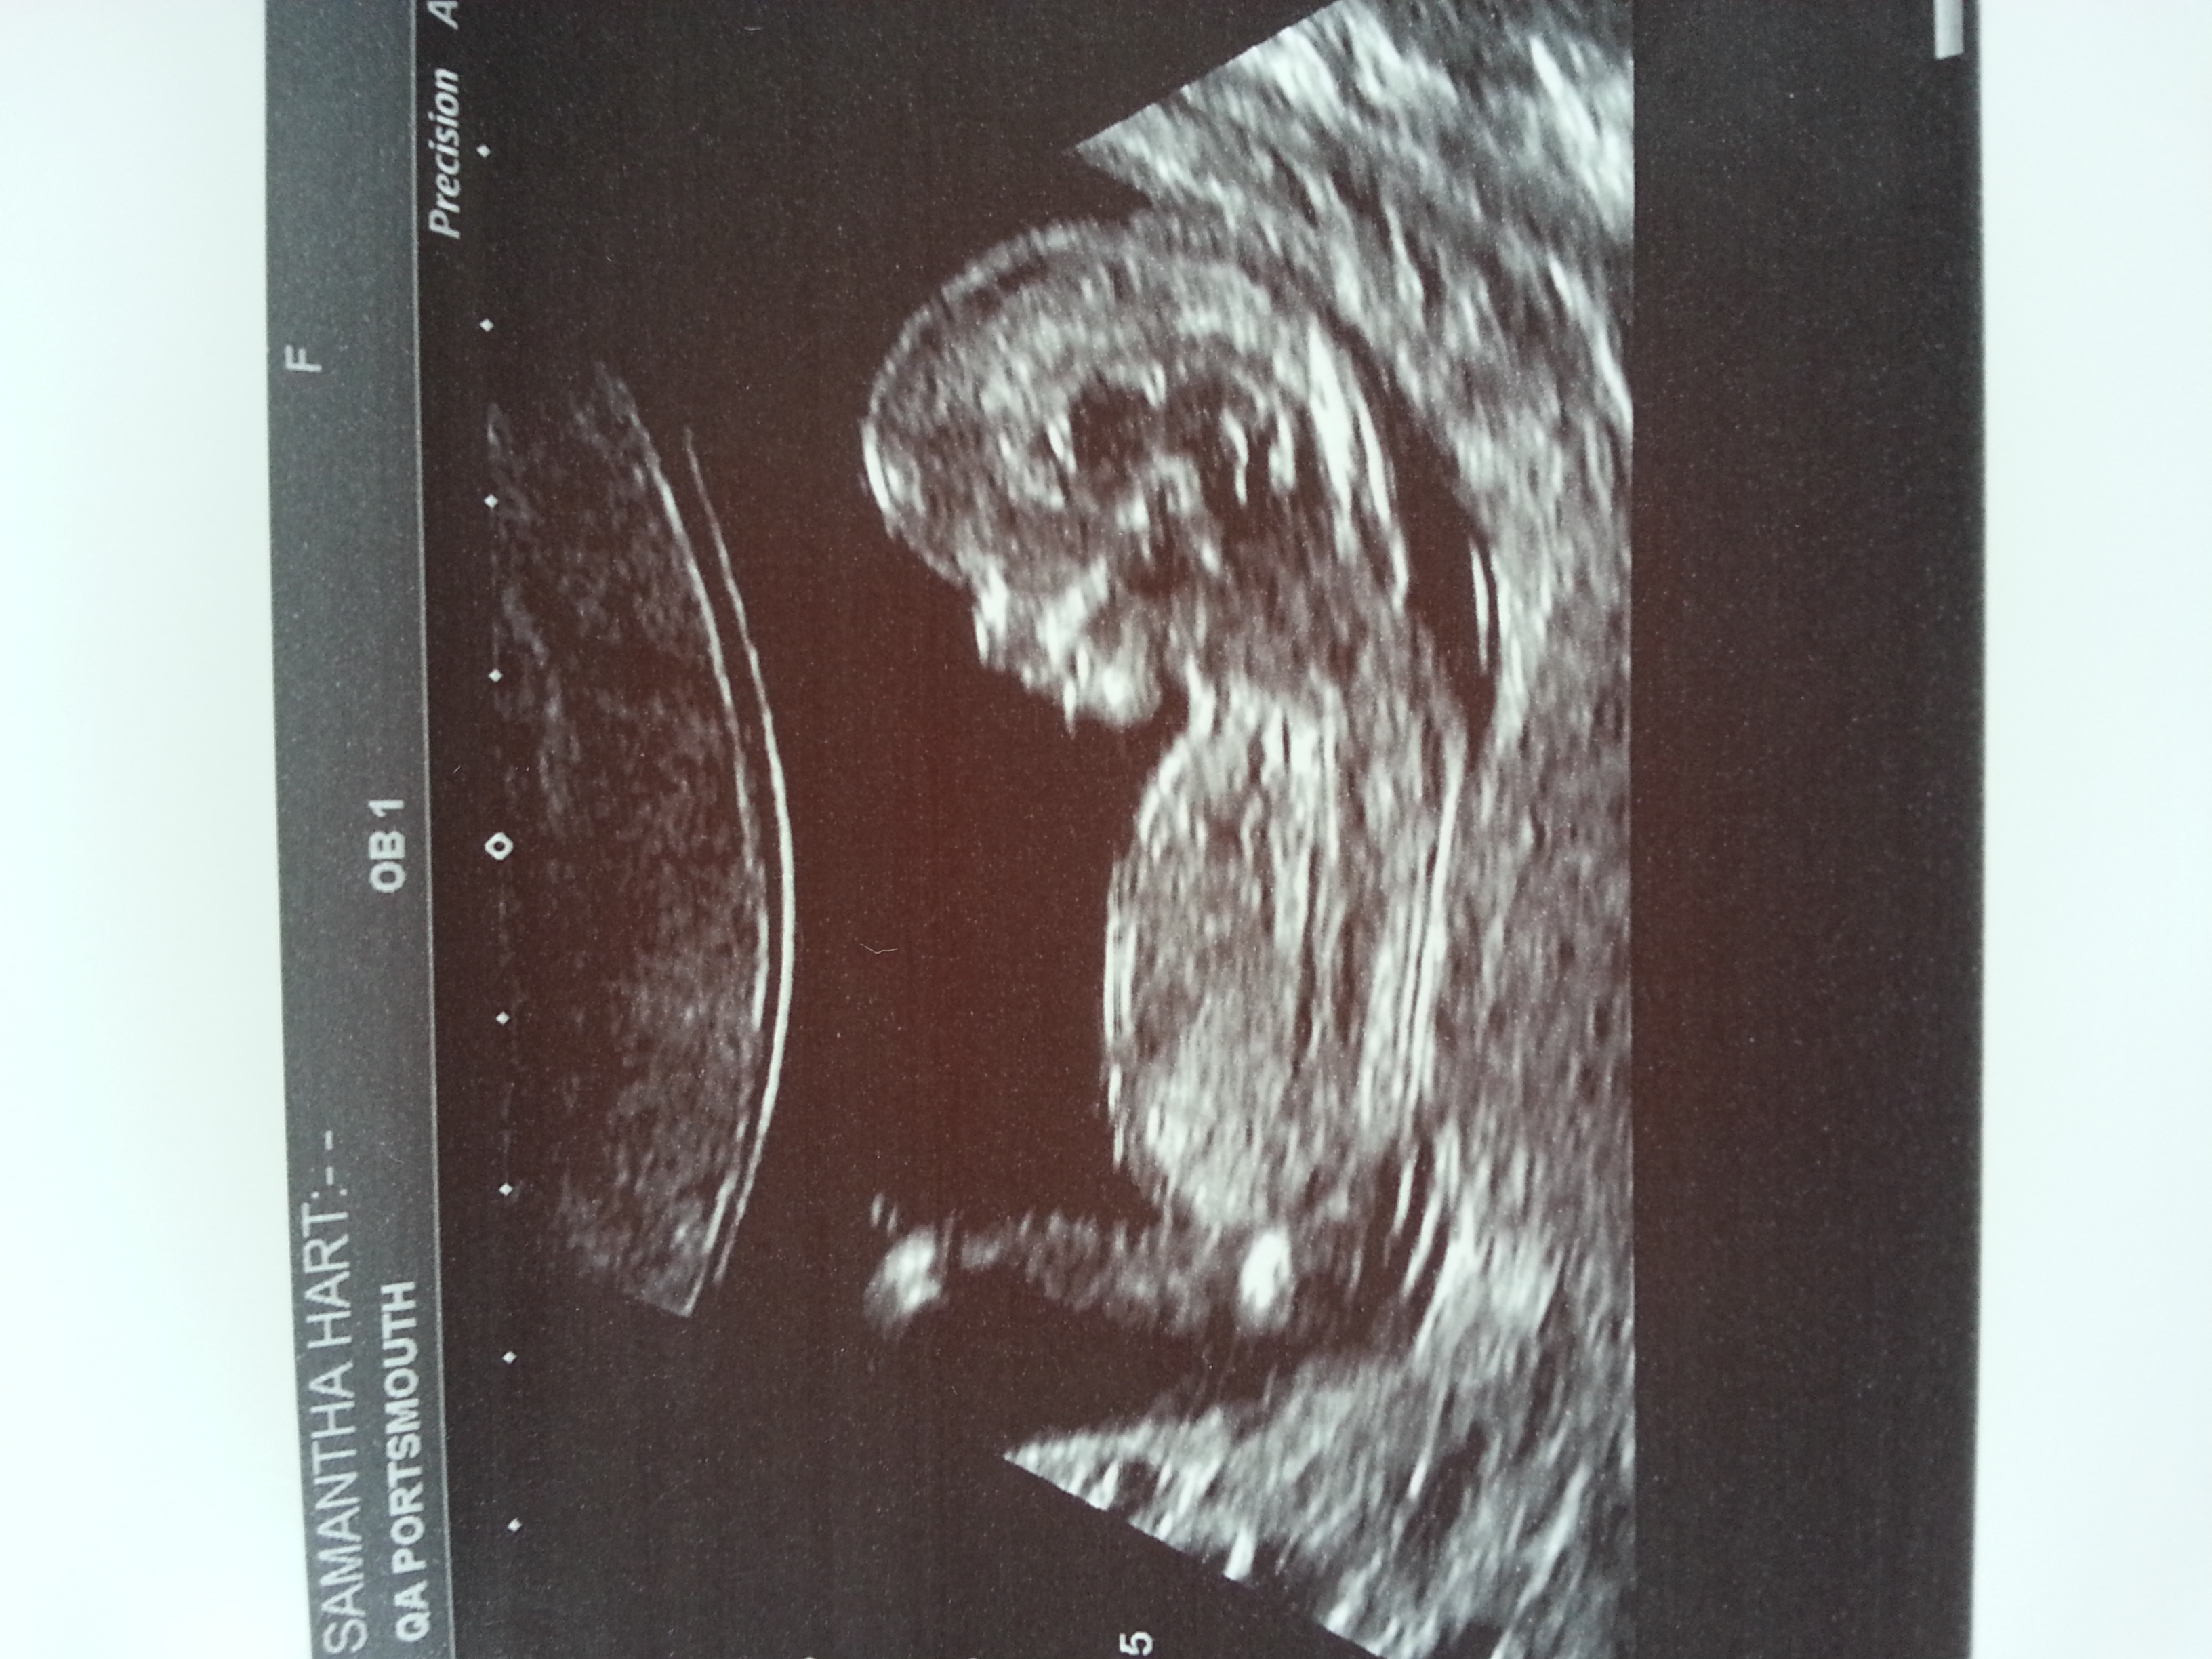

Not seeing any clues, sorry. Cute baby, though! x

by skull BOY

Boy guess Sent from my iPhone using Tapatalk

I lean boy.